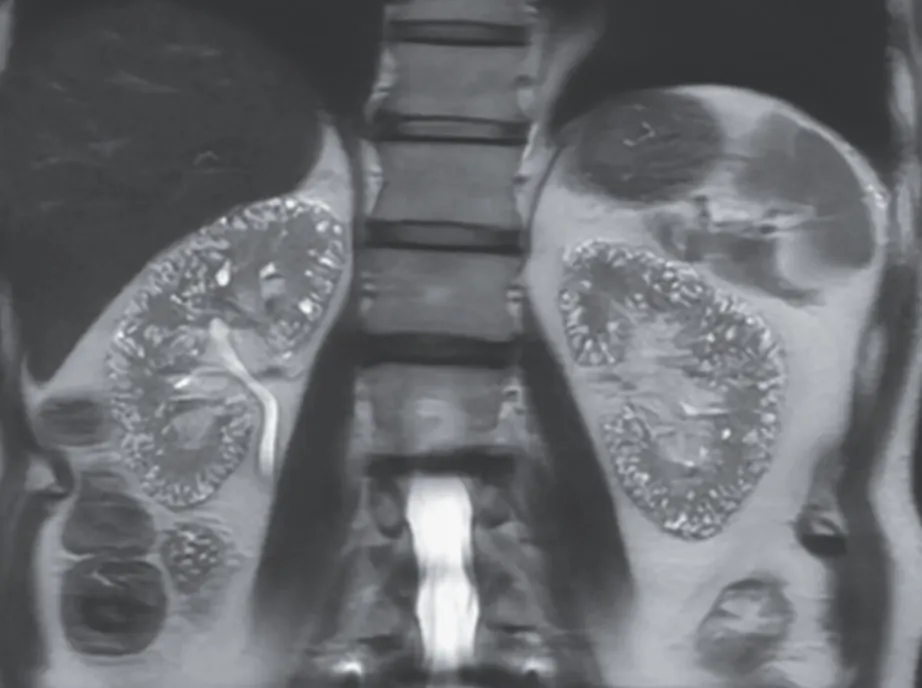

Microcistos renais e lítio: existe relação? O uso crônico de lítio pode impactar os rins, mas qual o papel dele na formação de microcistos renais? Entenda o que a literatura recente revela.

Valkercyo Feitosa

12 meses atrás